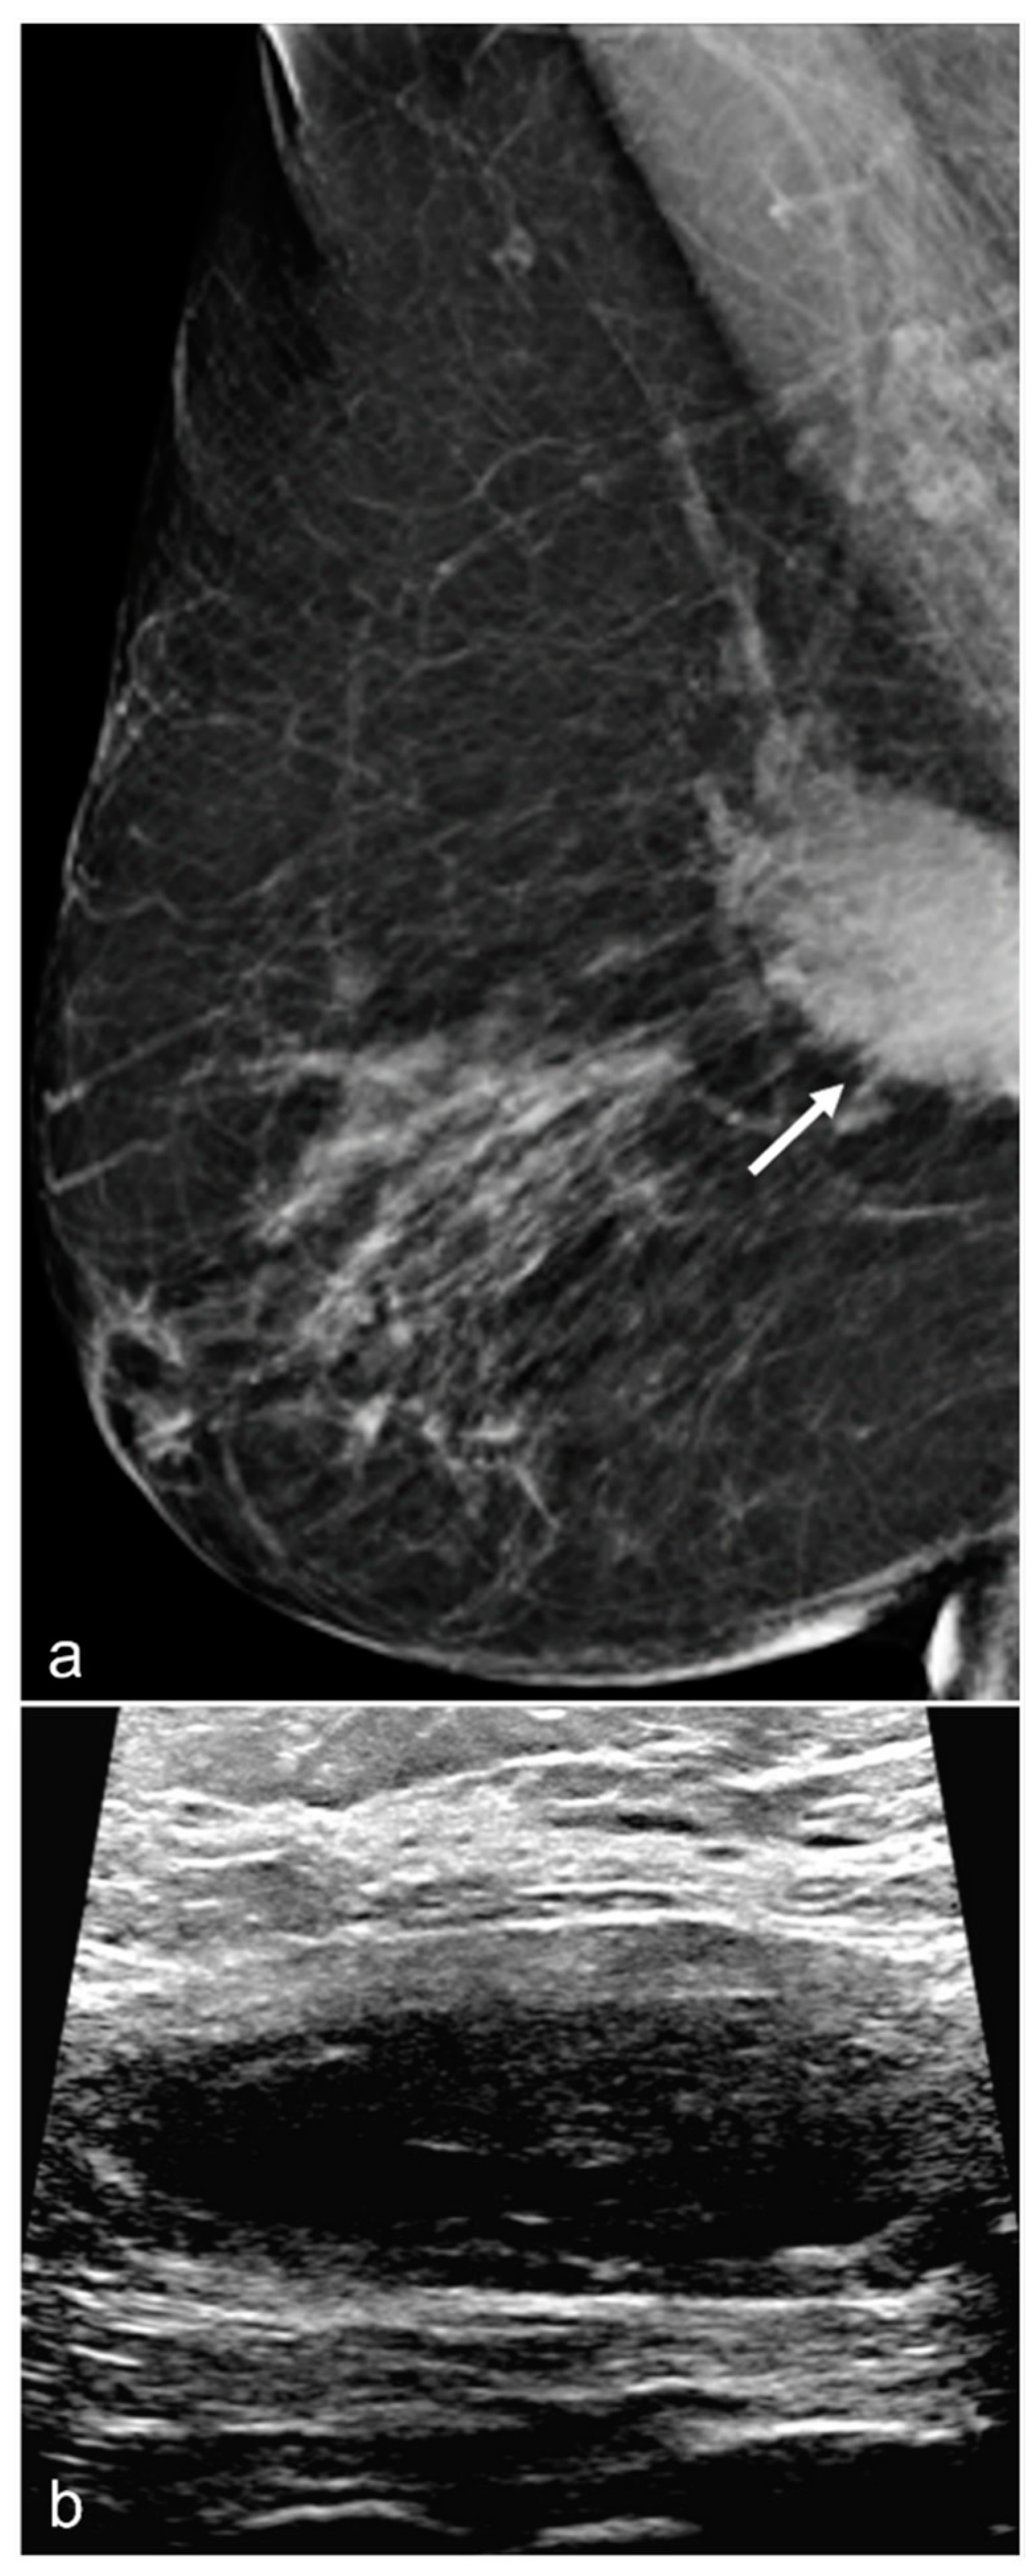

Figure 8. A 67-year-old woman with subglandular silicone implants developed a large, dense right subglandular mass (arrow) on mammography (a) two years after BES. Follow-up longitudinal right breast ultrasound (b) demonstrates a fluid collection with internal debris, confirming evidence of a seroma.